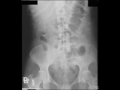

Neurofibromatosis on Abdominal X-ray

Patient with neurofibromatosis. Abdominal x-ray shows multiple round radiodensities compatible with neurofibromatosis on the skin (arrows). On abdominal x-rays, you would be unable to see intra-abdominal masses this small unless they were calcified. However, skin lesions are well visualized.